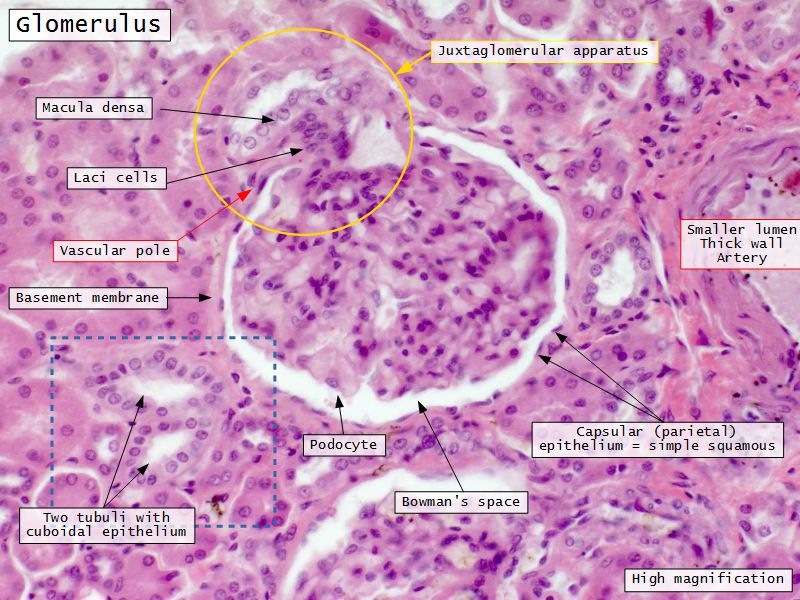

Renal corpuscle

- Tuft of capillaries

- grow into

- Blind end of nephron

- Several layers of epithelium

- Two sides

- Vascular pole

- Tubular pole

Blood flow

- Efferent arteriole

- Smooth muscle in media

- Capillaries

- Fenestrated

- Afferent arteriole

- Smooth muscle in media

Epithelium layers

- Capillary endothelium

- Visceral layer of epithelium

- Podocytes

- Resting on glomerular basement membrane

- Capsular space

- Parietal layer of epithelium

- Simple squamous epithelium

Juxtaglomerular complex

Area where distal convoluted tubule return to glomerulus and pass through the notch between the afferent and efferent arterioles. Modification of the wall of the tubule and afferent arteriole and presence of specialised cells in the connective tissue.Modifications

- Distal convoluted tubule

- Macula densa

- Narrow epithelial cells

- Nuclei densely packed

- CT cells

- Laci cells

- Similar to mesangial cells